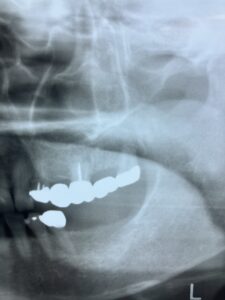

インプラントの上部構造の最終補綴物にメタルボンドと呼ばれるセラミックが使用されていました。今でも使用しますが1番の欠点として破折の可能性があることです。近年、物性や神秘性が格段に向上したジルコニアが、第一選択上がるようになりました。